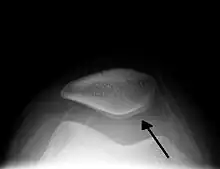

Image radio d'une hydarthrose du genou.

Elle est souvent localisée au genou (présence du signe du glaçon) et peut évoluer en kyste poplité.